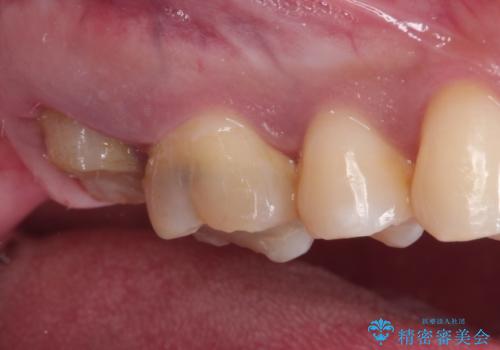

歯肉に埋もれたマージンライン 奥歯の被せもの

以前の被せもののマージンは歯肉縁下に深く形成され、根尖病変も認めたため、根管治療(林先生に依頼)、歯周外科、PGAクラウンにて修復治療を行いました。

妥協せずにすべての治療を行うことで最終的な被せものの適合を高める事ができます。今回のケースを保険の治療で行う場合は長期予後を望めないものとなります。